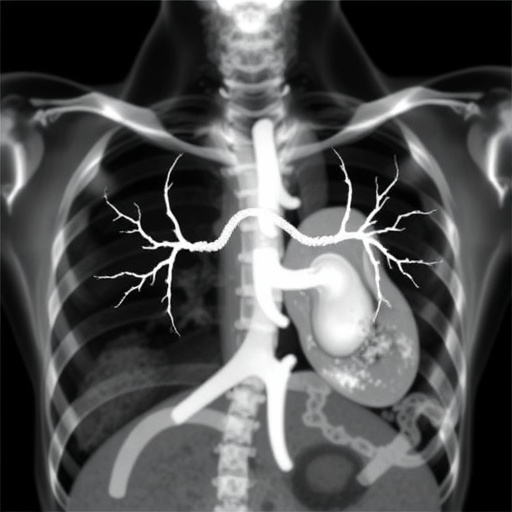

Image Credits: AI Generated